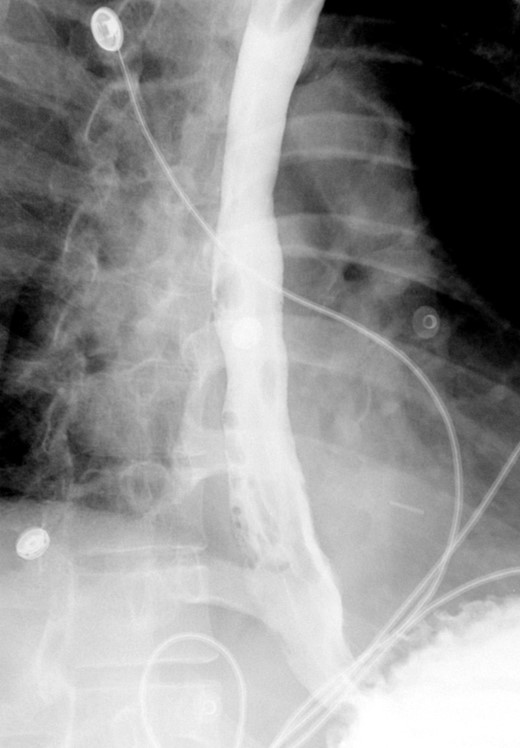

A computed tomographic scan revealed air and fluid surrounding the esophagus (Fig. 1). Esophagogram performed with water-soluble contrast media showed a distal esophageal perforation with a free leak into a large mediastinal cavity to the left of the esophagus (Fig. 2). The patient was triaged directly to the operation room. A left chest tube was placed with improvement in his oxygenation, and grossly murky fluid was drained. Esophagogastroduodenoscopy (EGD) was performed next and revealed a very small caliber esophagus with concentric ringed appearance. A tight stricture was noted in the mid-esophagus, which only allowed passage of a pediatric gastroscope. In the lower esophagus, a 2-cm tear with necrotic edges was visualized 3 cm above the gastroesophageal (GE) junction. With this diffusely strictured and very diseased appearance of the esophagus, the decision was made to proceed with stent placement and thoracoscopic drainage of the mediastinum rather than primary surgical repair via thoracotomy. A fully covered, 15 cm × 19 mm, EndoMAXX® esophageal stent was successfully placed covering the perforation site. Mediastinal washout and drainage was performed subsequently via left thoracoscopy. A postoperative esophagram showed no leak and the patient was started on a liquid diet that was tolerated well. His hospital stay was uneventful, and he was discharged on twice daily high-dose proton pump inhibitor (PPI) on post-operative Day 5. He was placed on a mechanical soft diet on discharge. Repeat upper GI study with water soluble contrast postoperatively showed no evidence extravasation. (Fig. 3)

Shows evidence of esophageal rupture and leak with pneumomediastinum and air and fluid surrounding the esophagus.

Demonstrates narrow esophageal caliber and extensive distal left thoracic esophageal leak approximately 3 cm proximal to the GE junction.